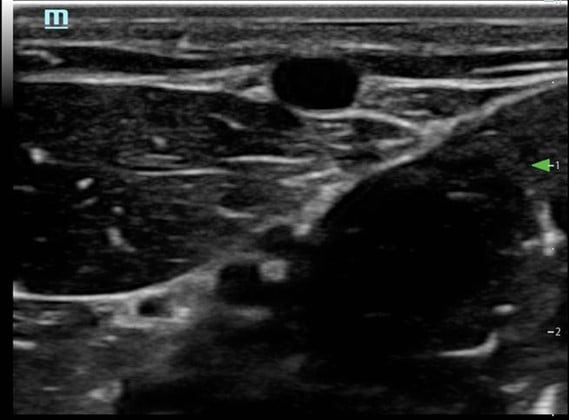

- Visualize the vein in cross-section (Fig. 3)

Figure 3. Short axis approach: vein visualized in cross axis

- Needle and vessel kept in the same plane (Fig. 6)

Figure 6. Long axis approach: Vessel appearance